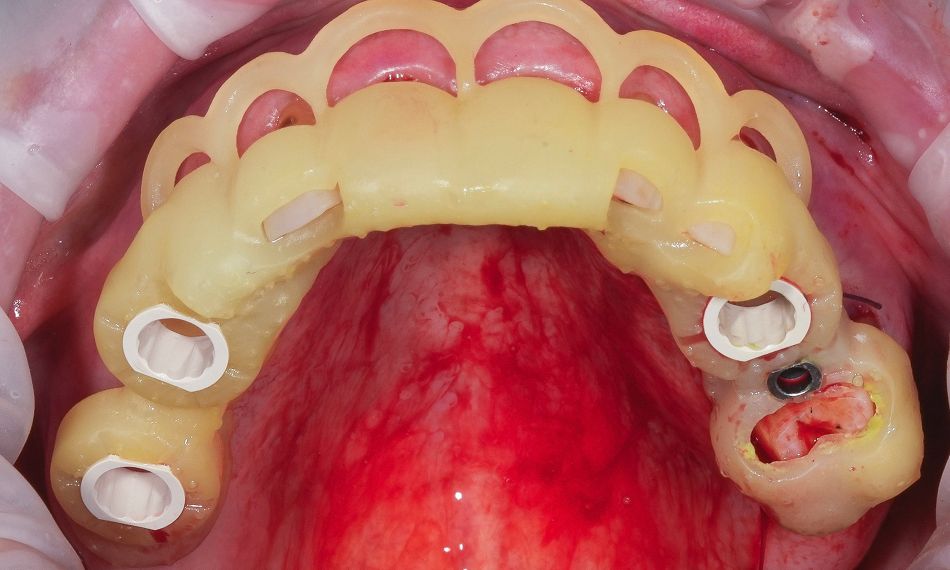

Early loading was applied to the four maxillary implants, while immediate loading was performed for the four mandibular implants. The provisional restoration was delivered the day after surgery using screw-retained abutments (SRA), torqued to 35 Ncm, and a screw-retained prosthesis that was picked up intraorally. The interim restoration was fabricated from CAD/CAM-milled PMMA, ensuring optimal fit, esthetics, and hygiene during the osseointegration period.

Three months after surgery, successful osseointegration was confirmed. A passive fit of the temporary restoration was achieved.

At the first appointment, a functional mock-up was fabricated to evaluate occlusion, esthetics, vertical dimension, and phonetics before proceeding with the definitive restoration (Fig. 15). The extraoral reverse scanning technique was used to digitally capture implant positions for prototype prosthesis fabrication. Three digital scans were acquired with an intraoral scanner (TRIOS 5, 3Shape). The first scan recorded the conversion prostheses in situ, capturing occlusal, palatal/lingual, and buccal surfaces, as well as the patient's occlusion. The second captured the soft tissue morphology of the arches with screw-retained abutments after prosthesis removal; and the third was an extraoral reverse scan of the prostheses with Straumann® RevEX™ scan bodies to accurately record the 3D implant positions and facilitate the design of the definitive prosthesis (Fig. 16).